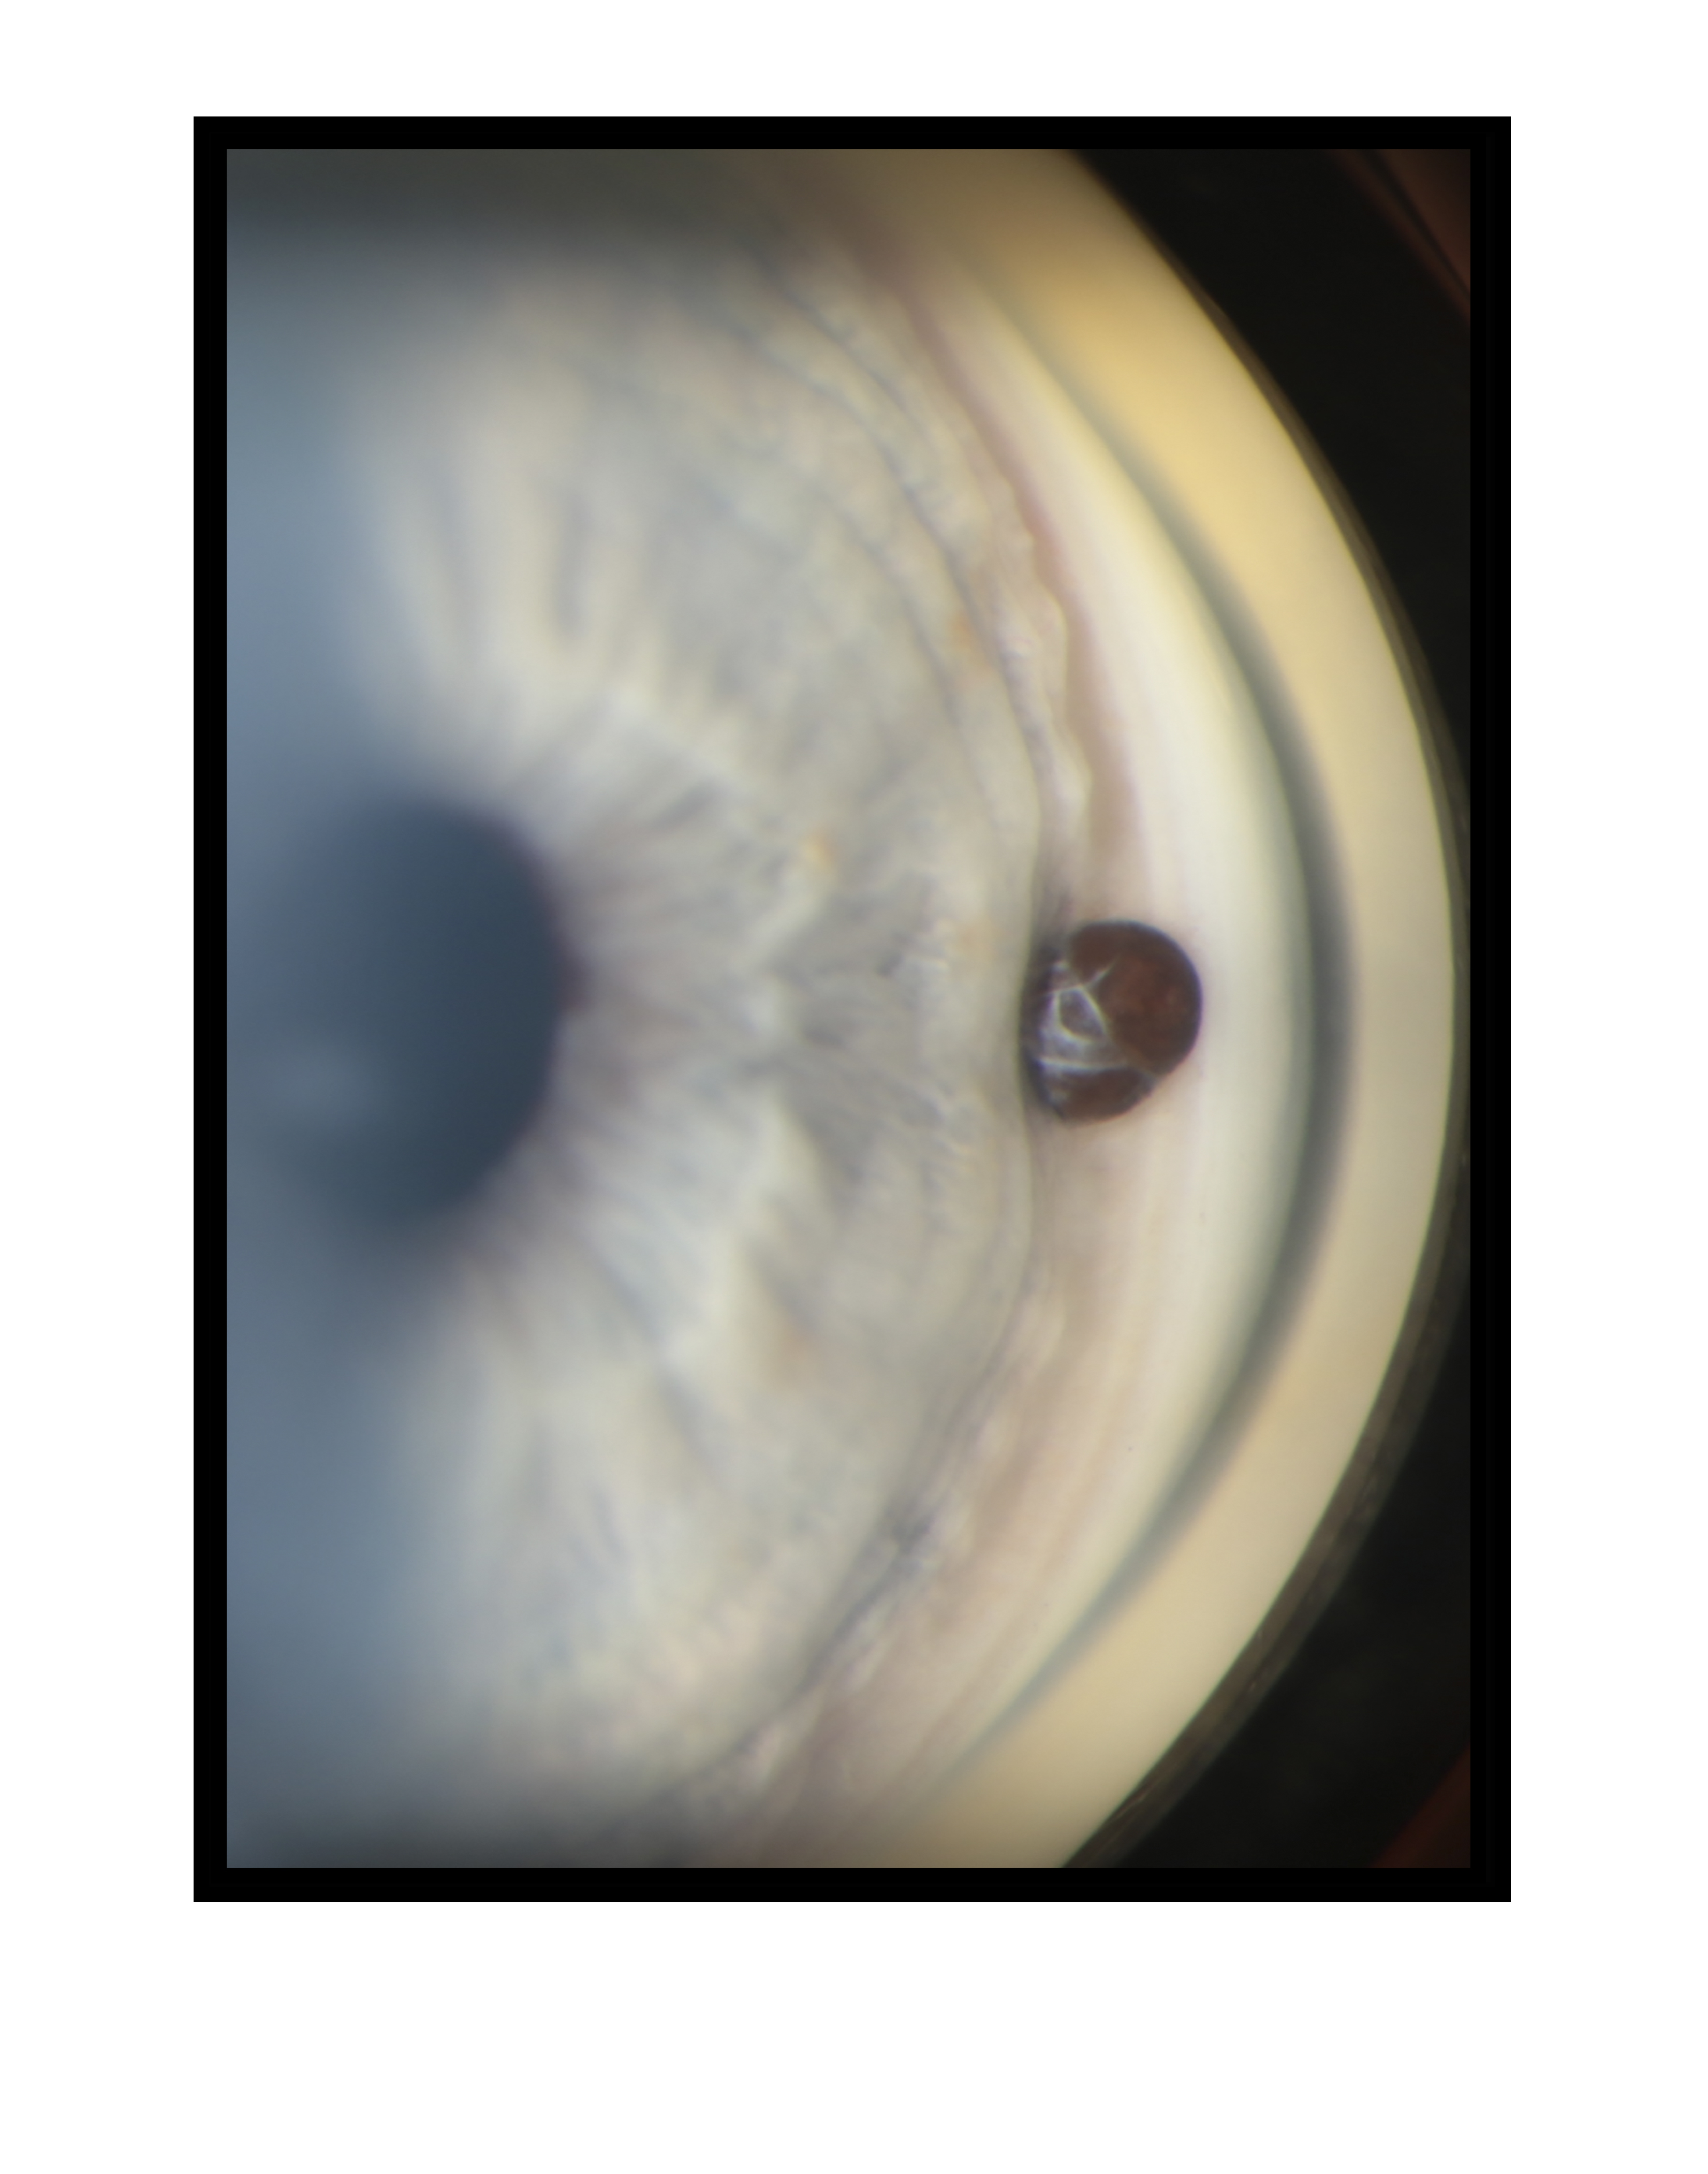

Iris Cyst Presented by Mark Harrod, CRA, OCT-C This photograph received Third Place in the category "Gonio Photography" and was displayed in the 2024 OPS Exhibit. Filed Under Cornea OPS Photo